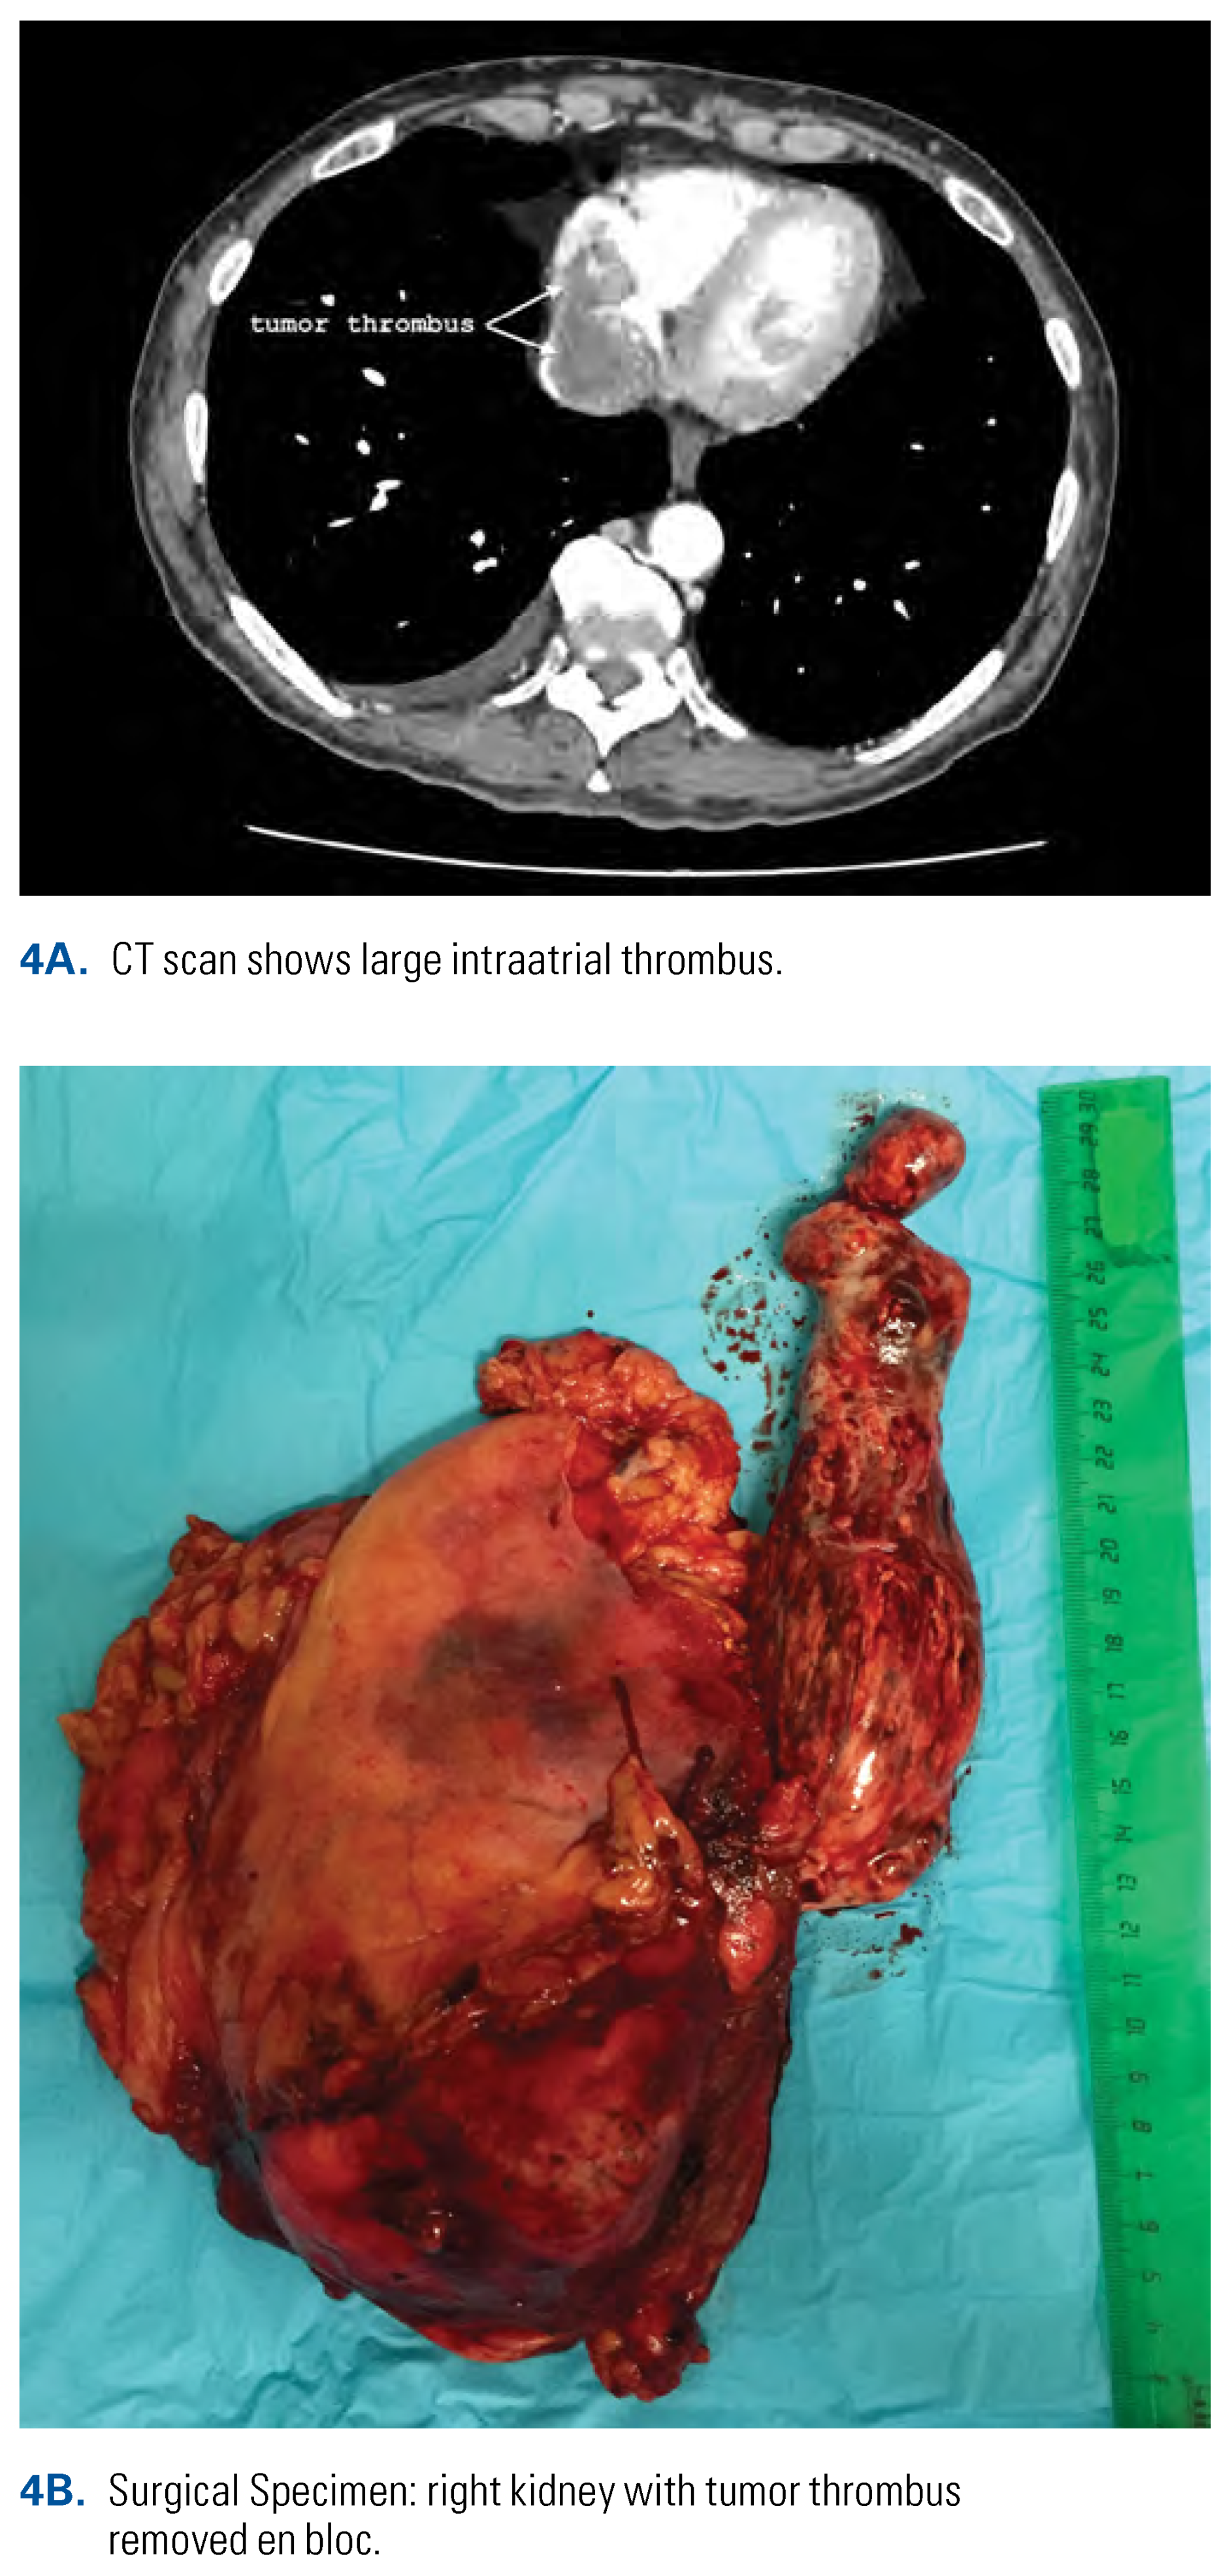

On the contrary, in the case of an intraatrial thrombus, the intrapericardial IVC needs to be completely mobilized so that it can be encircled at the cavoatrial junction. The diaphragm at the IVC hiatus must be completely mobilized from the IVC to widen the natural narrowing for safer extraction of the thrombus from the right atrium (Figure 3A) The upper tourniquet on the intrapericardial IVC is left unclamped until the apex of the thrombus is removed from the heart. After all other tourniquets are sequentially clamped with a Pringle maneuver, the incision of the retrohepatic IVC is continued up to the cavoatrial junction. The thrombus is gently mobilized from the retrohepatic IVC (Figure 3B). If the head of the thrombus is mobile, the retrograde blood flow from the right atrium will evacuate the thrombus. If the thrombus is adherent to the vessel wall, the incision is extended on the intrapericardial IVC and the thrombus is resected from the intima of the intrapericardial IVC under direct visualization. In the case of a large head of the tumor thrombus, the incision may even be extended 5 to 10 mm on the right atrium wall (Figure 4). As soon as the thrombus is evacuated from the right atrium and the intrapericardial IVC, the upper tourniquet is closed. The rest of the procedure progresses as described above for patients with level III thrombus.

Figure 4. Radical nephrectomy with thrombectomy in cT3bN0M0 RCC of the right kidney with large intraatrial level IV tumor thrombus.